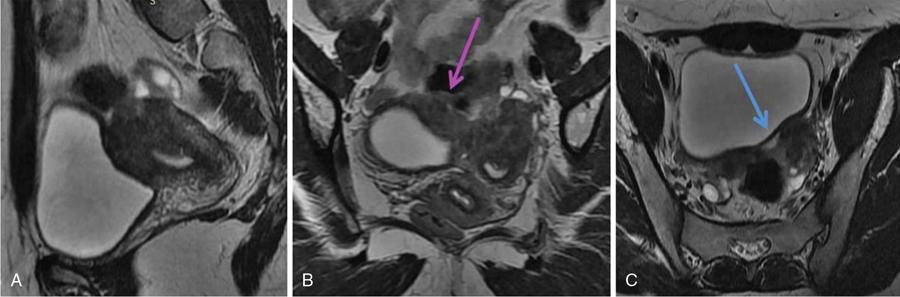

MÜLLERIAN DUCT ANOMALIES Rajani Gorantla Müllerian ducts are a pair of tubular structures that give rise to uterus, cervix, fallopian tubes and upper two-thirds of vagina. Disruption or failure of normal development can result in occurrence of Müllerian duct anomalies (MDAs). These are commonly associated with other congenital anomalies of urinary tract and ovaries due to the close relationship between the development of mesonephric and paramesonephric ducts; few patients also have associated skeletal system anomalies. The prevalence of MDAs in an unselected population was 5.5%; 8% among the infertile women, 12.3% in women with a history of recurrent pregnancy loss and 24.5% in women with miscarriage and infertility. Most of the patients with MDAs are asymptomatic and found incidentally on imaging for any other gynaecological problems, in evaluation of a patient with renal, skeletal or abdominal wall abnormalities. In symptomatic women, complains are related to the type, severity, obstructive anomaly or nonobstructive anomaly. The symptoms can be obstetric or gynaecological related, includes recurrent spontaneous abortions, infertility, preterm labour, intrauterine growth restriction and abnormal foetal lie. Few adolescent girls may present with primary amenorrhoea, hypomenorrhoea, abnormal vaginal bleeding, cyclical pain and mass. Rarely they can present with pelvic inflammatory disease with abnormal vaginal discharge, dyspareunia and urinary tract infections. The female reproductive system develops from a pair of Müllerian or paramesonephric ducts, urogenital sinus and vaginal plate. The ovaries develop separately from the primordial ridge. It is of great importance to understand the normal stages of development, as failure or interruption of any of these stages can lead to a simple to complex spectrum of anomalies. The three stages of Müllerian duct development include: At 6–10 weeks of gestation age, two paired Müllerian ducts and Wolffian ducts formation occurs. When Y chromosome factor (testicular determining factor) is absent, the Wolffian ducts undergo degeneration. The Müllerian ducts further elongate caudally and cross the Wolffian ducts to fuse in the midline. At 10–13 weeks of gestation age, caudal and lateral fusion of the two Müllerian ducts forms primitive uterovaginal canal, which is possessed of solid tissue initially located side by side and further internal canalization leads to the formation of two channels/canals divided by a septum. At this stage, there is reabsorption of the caudal septum and forms single cervical canal and vagina lumen. In around 15–20 weeks of gestation age, complete resorption of the septum takes place in a caudocranial direction from the isthmus to fundus and development of single endometrial cavity results. The fused caudal part of Müllerian ducts gives rise to the uterus, cervix and upper two-thirds of vagina; the unfused cranial part forms the fallopian tubes (Fig. 11.14.1.1). The lower vagina develops from the urogenital sinus, which is separated from the rectum by urorectal septum around 7 weeks of gestation age. The primitive uterovaginal canal embeds into the dorsal wall of urogenital sinus and forms Muller’s tubercle. Around 13 weeks of gestation, two solid masses known as sinovaginal bulbs originate from the upper part of the Muller’s tubercle, further proliferate into the caudal end of the uterovaginal canal to become a solid vaginal plate. Later canalization or degeneration of the central cells of the vaginal plate forms the lower vagina, which is usually completed by 20 weeks’ gestation. The vertical fusion of the upper and lower vagina occurs with resorption of tissue in between and forms single vaginal cavity (Fig. 11.14.1.2). The vaginal lumen is separated from the urogenital sinus by the hymenal membrane. Just before birth, the hymen normally ruptures due to retrogression of the central epithelial cells. However, a thin fold of mucous membrane persists around the vaginal introitus. The ovaries develop separately from migration of primordial germ cells to the genital ridge. Ureteric buds develop separately and concurrently. So renal anomalies are most commonly associated with MDAs with an association of 30%–50%. Various classification systems have been proposed over the past several decades to describe MDAs. Ideally, same classification system needs to be followed by a gynaecologist, surgeon and radiologist for better communication. Buttram and Gibbons classification was suggested in 1979, and it was based upon the level of failure in normal development and segregate the anomalies into groups with similar clinical manifestations, treatment, and prognosis for foetal salvage. According to Buttram and Gibbons, the uterine anomalies were classified into six classes as described in Table 11.14.1.1. The drawback is the lack of classification of vaginal and other anomalies separately. The ASRM (previously the American Fertility Society – AFS) classification system is the most widely accepted classification worldwide over the past years and was introduced in 1988. According to this classification, MDAs are classified into seven classes (class I to class VII) as mentioned in Table 11.14.1.2. However, several limitations have been described by Grimbizis and Campo in 2010 (Fig. 11.14.1.3). The drawbacks of the ASRM classification system are as follows: Hence in 2016, an updated classification of uterine septum, that is ASRM-2016 was proposed and officially approved morphometric criteria are given for distinguishing between septate, normal/arcuate and bicornuate uteri (Table 11.14.1.3). The VCUAM classification was proposed in the year 2005. The main concern is to provide a simple, systematic, clinical classification in addition to providing a precise reflection of the entire malformation. The female genital organs were divided into the following subgroups in accordance with the anatomy: vagina (V), cervix (C), uterus (U) and adnexa (A). Associated malformations were assigned to a subgroup (M) relative to each specific organ. The disadvantage is due to its inherent complexity, and more than 56,700 individual combinations of anomalies are possible. ESHRE and ESGE established a common working group named CONgenital UTerine Anomalies (CONUTA) in order to devise an improved classification system (Table 11.14.1.4). It was published in 2013. Anatomy is the basis for systemic categorization of the MDAs. The subclasses are divided by the different degrees of uterine deformity and their clinical significance (Fig. 11.14.1.4). Cervical and vaginal anomalies are classified into independent supplementary subclasses (Figs. 11.14.1.5–11.14.1.6). For most of the clinicians, it helped as starting point for the development of guidelines for their diagnosis and treatment. The malformations are graded according to severity, U0–U5, C0–C4 and V0–V4, with U5, C4 and V4 being more severe. Class U3 incorporates bicorporeal fusion defects (didelphys and bicornuate) as this was considered as a more functional mode of classification. Arcuate uterus was not included separately, but this is categorized under normal variant into class U1c. Recent studies have demonstrated that the ESHRE/ESGE system provides an effective and comprehensive classification for almost all the currently known MDAs and overcomes the limits of previous classifications. However, there is a relative overdiagnosis of septate uterus with the application of ESHRE–ESGE criteria has been reported and which potentially might lead to unnecessary surgical overtreatment. C0 C1 C2 Normal cervix Septate cervix Double ‘normal’ cervix C3 C4 Unilateral cervical aplasia Cervical aplasia U4 V0 V1 V2 V3 Normal vagina Longitudinal nonobstructing vaginal septum Longitudinal obstructing vaginal septum Transverse vaginal septum and/or imperforate hymen V4 Vaginal aplasia C MDAs’ characterization and classification is of great significance, as the treatment is determined by the type and severity of abnormality. The various imaging modalities available include: HSG was the most recognized imaging modality, earlier to the development of the ultrasonography (USG) and MRI. It is an invasive fluoroscopic-guided procedure for uterine and tubal assessment, and is performed during the midproliferative phase of the cycle, ideally between days 7 and 10 of the cycle when endometrium is thin. Fluoroscopic spot images obtained to evaluate uterine configuration, uterine filling defects and fallopian tube patency. HSG allows evaluation of only the component of the uterine cavity that communicates with the cervix. The anatomic information about myometrium and external fundal contour will not be provided by HSG. The diagnostic criteria used to diagnose MDAs on HSG include: HSG findings of different MDAs are described in Table 11.14.1.5 and Fig. 11.14.1.10. Virtual HSG is a noninvasive technique performed by using a computed tomography (CT) scanner, done 45 s after the contrast material instillation begins. Contraindications are similar to those for HSG and include pregnancy and active pelvic infection. There is no necessity for retraction of the uterus or manipulation of the cervix. The procedure is quick, easy and prophylactic administration of antibiotics is not required. The use of a power injector helps to ensure a steady low pressure of instillation. The procedure is less painful, more comfortable and easily tolerated by patients than conventional HSG. Radiation exposure sometimes requires cervical clamping, which may result in complications such as bleeding and infection. Transabdominal pelvic ultrasound can diagnose uterine anomalies with accuracy rate of 47%. Two-dimensional transvaginal ultrasound (TVUS) has high sensitivity and specificity than transabdominal study and provided some information about external and internal fundal contours. The detection rate is high if the scan is performed in secretory phase due to better visualization of endometrium. Three-dimensional USG shows great accuracy than 2D USG in evaluation of the uterine morphology. The technique of 3D USG varies with different vendors. It displays both the external and internal fundal contours and lower uterine segment by acquisition of single coronal view of uterus (c-view) (Fig. 11.14.1.11). The only disadvantage is that it is transvaginal study and shall not be done in paediatric age group and sexually inactive women. Three-dimensional TVUS has become the first line of screening tool in most of the infertility clinics as it is noninvasive, faster, repeatable, allows storage of volume data and has multiplanar capability for systematic evaluation of the uterine and cervical cavities. The salient features of various Müllerian anomalies on 3D USG are described in Table 11.14.1.6 with images. Three-dimensional ultrasound is combined with sonosalpingography in this technique and provides better delineation of the uterine morphology. It is a less invasive procedure done in proliferative phase with instillation of saline into the uterine cavity and assessment of the uterus will be done. MRI is a universally accepted imaging modality in the documentation of MDAs and accuracy rate of 100% have been reported. MRI provides excellent delineation of both the internal and external uterine anatomies. T2-weighted (T2W) images are the mainstay of pelvic imaging and are performed without fat suppression. T1-weighted (T1W) images are mainly for the haemorrhagic content. The disadvantages of MRI include time-consuming procedure, not cost-effective, large body habitus, pacemakers, recent surgical history and claustrophobia. The current and proposed MRI protocol given by the European Society of Urology (ESUR-MRI protocol) intends a dedicated evaluation of MDAs as mentioned below (Fig. 11.14.1.12): Vaginal anomalies can be accurately diagnosed with the prior administration of the ultrasound gel, to distend vagina (Fig. 11.14.1.13). It will help in better diagnosis of complex vaginal anomalies, like vaginal septations or vaginal duplication. The normal MRI appearance of uterocervical canal and vagina are shown in Fig. 11.14.1.14. Uterine aplasia/hypoplasia/agenesis is class 1 MDA according to ASRM classification and U5 uterine anomaly according to ESHRE classification. It is a formation defect of the paramesonephric ducts with complete or segmental agenesis of uterus and vagina. The incidence rate is around 10%–15% of all MDAs and considered as the most severe form of uterine anomaly. Most of them have complete uterovaginal agenesis with no single completely developed uterine cavity and are associated with Mayer–Rokitansky–Küster–Hauser syndrome (MRKHS). Two types of this syndrome are depicted. The typical form or type A represents the absence or remnants of the uterus, cervix, upper two-thirds of vagina with normal ovaries and fallopian tube (Fig. 11.14.1.15). The atypical form or type B is associated with the abnormalities of the ovaries, fallopian tubes and genitourinary system (Fig. 11.14.1.16). In a few cases (approximately 10%), unilateral or bilateral uterine remnants and with or without endometrial cavity will be seen (Fig. 11.14.1.17). Most of them present with primary amenorrhoea due to complete uterovaginal agenesis and manifest as MRKHS. These patients have normal secondary sexual characteristics due to the preserved normal ovarian function and phenotype. If uterine remnants with functional cavity is present, will present with cyclical pain along with amenorrhoea due to cryptomenorrhoea and haematometra. USG is the first modality for identification of these anomalies, absence of uterus with normal ovaries is diagnostic. But, it is difficult to locate the uterine remnants and cavity due to small acoustic window. MRI is the gold standard and it classifies into uterovaginal agenesis and hypoplasia. If hypoplasia is identified, sagittal and axial sections are taken. These remnants are seen as T2 hypointense tubular structures, located in close relation to ovaries in the adnexa. Once we identify the uterine remnants, it is important to look for the functional endometrial cavity. These will have reduced endometrial and myometrial width. MRI can easily delineate the zonal anatomy due to its high soft tissue contrast resolution. The management of Müllerian agenesis consists of counselling for the patient and her parents. Some patients with MRKHS opt for creation of neovagina for normal sexual life. Various techniques are available. In the presence of a functional Müllerian remnant, regardless of whether it is communicating or not, medical suppression of menses can be initiated and should be followed by laparoscopic removal of the hypoplastic remnant. Unicornuate uterus or hemiuterus is defined as the unilateral uterine development and the contralateral Müllerian duct could be either partially formed or absent. It is a formation defect and the necessity to classify it in a different class than that of uterine agenesis, which is also a formation defect, is due to the existence of a fully developed functional uterine hemicavity. It is considered as class II anomaly according to ASRM classification and class U4 according to ESHRE classification. The frequency rate is around 20% of MDAs. Renal anomalies most often occur in association with unicornuate uterus and usually on the same side of uterine agenesis. Further unicornuate uterus is divided into two subclasses depending on the presence or absence of a functional rudimentary cavity in ESHRE classification: In ASRM classification, unicornuate uterus is divided into four subcategories: Mostly asymptomatic and presence of the noncommunicating uterine remnants will be identified at the time of infertility work up or caesarean section. If a functional cavity is present, the presentation is dysmenorrhoea or haematometra in an adolescent. The common obstetrics-related complications include abnormal foetal lie, intrauterine growth retardation, preterm delivery, placental abnormalities and uterine rupture. Gynaecological complications are ectopic pregnancy and endometriosis due to retrograde menstruation. On imaging, unicornuate uterus is seen as tubular and fusiform or banana-shaped structure at paramedian location, the endometrium is narrow and tapers to the apex with normal myometrial anatomy and reduced uterine volume. The rudimentary cavity or remnants are better depicted on 3D USG (Fig. 11.14.1.18) and MRI. However, MRI is superior to USG due to its high soft tissue resolution. The rudimentary cavity can communicate with main cavity or connected by fibrous band. The nonfunctioning cavity will be seen as T2 hypointense structure with loss of zonal anatomy (Figs 11.14.1.19 and 11.14.1.20), whereas the functioning cavity will show the deformed zonal anatomy (Fig. 11.14.1.21), and its complications like haematometra as T1/T2 hyperintense endometrial collection. Unicornuate uterus without rudimentary cavity does not require any procedure. But in the presence of communicating or noncommunicating rudimentary horn, surgical resection must be considered to prevent complications. Uterine didelphys is a class III MDA based on the ASRM classification and class U3b bicorporeal uterus according to ESHRE classification with an incidence rate of 5% among the uterine anomalies. It is a lateral fusion defect; results from complete failure of the Müllerian duct fusion. Two noncommunicating endometrial cavities with preserved zonal anatomy are seen with separate cervix. According to ESHRE classification, it is defined as external fundal indentation completely dividing the uterine corpus up to the level of external cervical os. It is most commonly associated with longitudinal vaginal septum in around 75% of cases. Some patients may show transverse vaginal septum and these will be obstructive or nonobstructive type. Renal anomalies are also commonly associated with uterine didelphys. Uterine didelphys is usually asymptomatic and diagnosed incidentally on pelvic examination or caesarean section. The uterine didelphys with obstructed vagina (Fig. 11.14.1.22) will present at adolescence as dysmenorrhoea, haematometrocolpos and haematosalpinx. Sometimes retrograde menstrual flow can cause endometriosis and pelvic adhesions. Obstetric-related complications include abortion/foetal growth restriction and poor pregnancy outcome. The uterine didelphys with obstructed hemivagina due to transverse vaginal septum and associated ipsilateral renal agenesis are the manifestations of the syndrome called obstructed hemivagina and ipsilateral renal agenesis anomaly/Herlyn–Werner–Wunderlich (HWW) syndrome (Fig. 11.14.1.23).